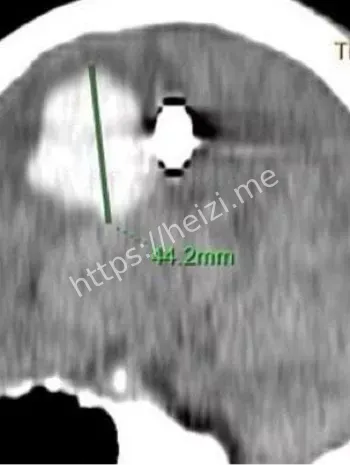

话说回来,这颗子弹是怎么射进去的?哎,八卦起来总得挖挖根儿啊!据说这是个意外,孩子可能在附近玩气枪游戏,或者大人不小心操作失误,结果这玩意儿就钻进了小脑袋。气枪这东西,看起来像玩具,威力却不小,尤其是对小孩儿,头部中弹直接就是脑损伤大麻烦。金边这地方,热带气候,孩子们爱在户外疯玩,但安全教育跟不上,类似意外时有耳闻。这次事件一出,大家都开始反思:家长们得多盯着点啊,别让好奇心变成灾难。医院那边也没闲着,术前他们得先做一堆检查,CT、MRI啥的,全方位扫描,确保手术路径最安全。

哇塞,高科技这时候就闪亮登场了!坤塔帕花儿童医院这次牛就牛在用了德国最新一代的蔡司显微镜,这玩意儿放大倍数高到能看清脑神经末梢,手术精度直逼毫米级。8小时里,医生们通过这镜子,避开血管和重要脑区,一点点剥离子弹周围的组织。别小看这设备,它不光帮着看清,还能实时监控出血情况,避免二次损伤。说白了,这技术让儿童脑手术从“盲人摸象”变成“高清直播”,风险降了好几成。金边这家医院本就是儿科重镇,引进这种前沿玩意儿,简直是为东南亚小孩儿开了扇希望之窗。